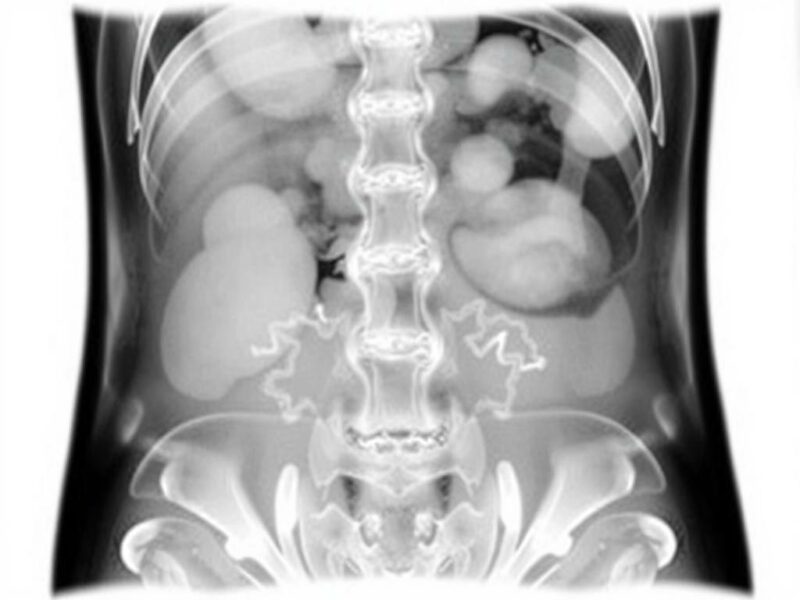

Principios físicos relevantes: por qué la radiografía falla en tejidos blandos

Para entender las limitaciones, conviene recordar lo básico: la radiografía aprovecha diferencias de atenuación entre tejidos (gas, grasa, agua/tejidos blandos, calcio/hueso). El abdomen presenta una mezcla compleja de aire intestinal, contenido líquido, grasa visceral y estructuras sólidas (hígado, riñón, páncreas, bazo), muchas de ellas con contraste de atenuación muy similar. Esta falta de contraste intrínseco hace difícil distinguir procesos inflamatorios o isquémicos del parénquima normal. Además, las proyecciones bidimensionales superponen órganos y asas intestinales, generando «ruido» anatómico que puede ocultar o simular patología. Por eso, un proceso inflamatorio del apéndice o una pequeña colección retroperitoneal suelen pasar desapercibidos en una radiografía simple.

- Lesiones retroperitoneales y masas sólidas: tumores renales, adenopatías retroperitoneales, abscesos en localizaciones profundas pasan inadvertidos o se confunden con asas intestinales.